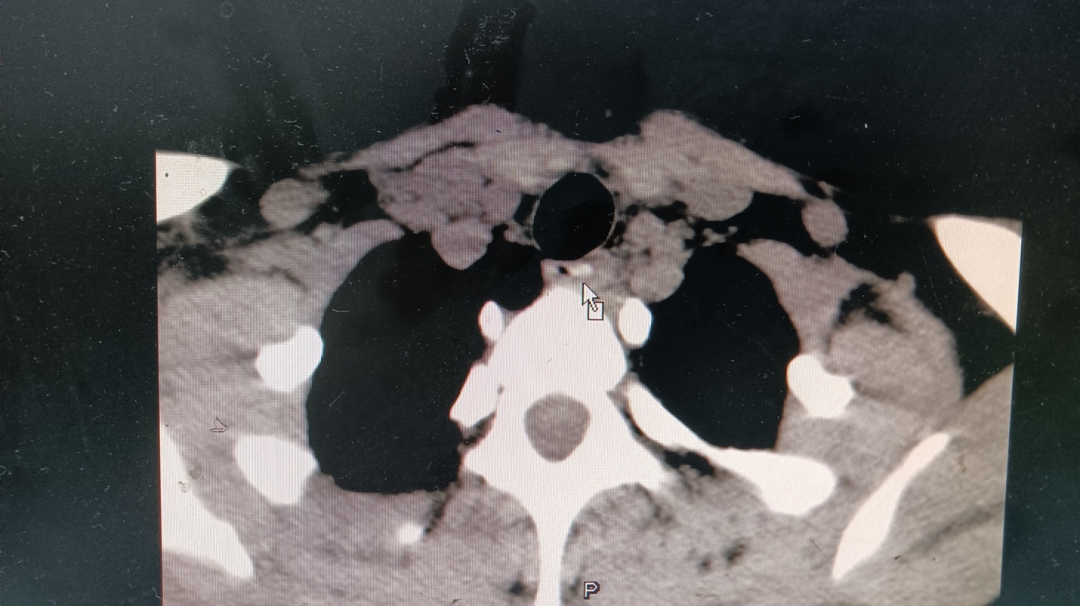

在搜索到的案例里,我并没有看到用CT检查食管异物的情况,不知道CT在这种情形下是否有些“大材小用”了。医生后来告诉我,根据2020年成人食管异物指南, CT 扫描是食管异物的首选影像学检查手段。它不仅能发现异物,还能通过图像推断异物在食管内的位置、异物本身的形状、大小等,有助于更好地选择治疗手段。

CT结果出来,确认了异物的存在,并且发现它位于第一胸椎水平处。有可能是一开始卡在食道入口处(第一狭窄),后来一番折腾让它向下移动了一些。医生告诉我,这种情况一般自己很难处理,因为食道有三个狭窄处,过了一关还会有下一关。

鼠标所指即为CT下疑似异物所在丨作者供图